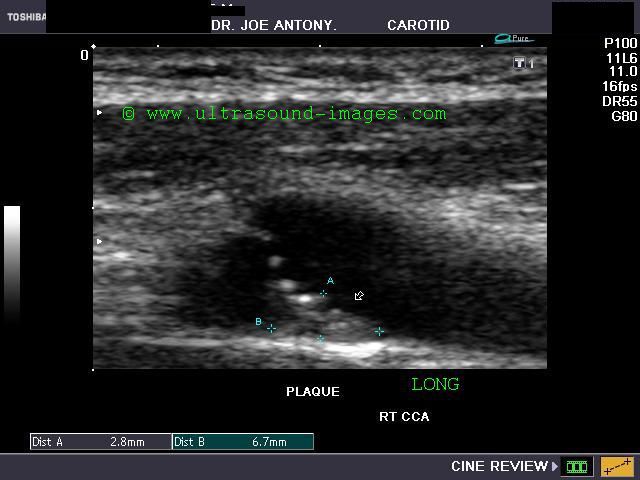

Case-2:Carotid artery plaque with calcification and ulceration

This elderly patient shows a calcific plaque in the right common carotid artery just below the bifurcation. This is a common site for plaque formation. This plaque also shows ulceration of the surface which further complicates the situation increasing the possibility of embolism.The plaque measures about 2.8 mm. in thickness and is 4 x 7 mm in dimension. Color Doppler ultrasound image above shows no significant obstruction (less than 50 % stenosis) to the flow through this area of the carotid artery.The color Doppler and spectral Doppler ultrasound images show and confirm the extent of ulceration of the surface of the carotid plaque. The degree of stenosis of the common carotid artery does not appear to be significant.